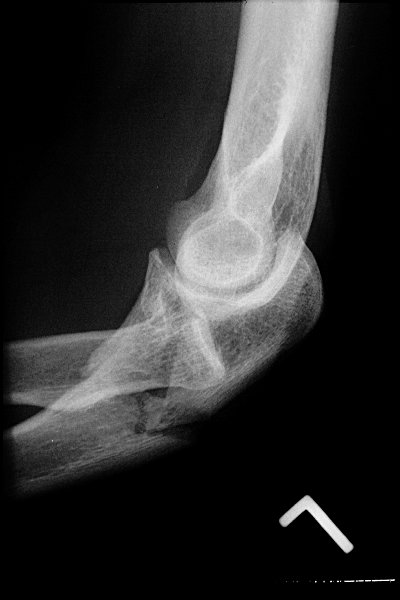

Return to Monteggia Fracture-Dislocation